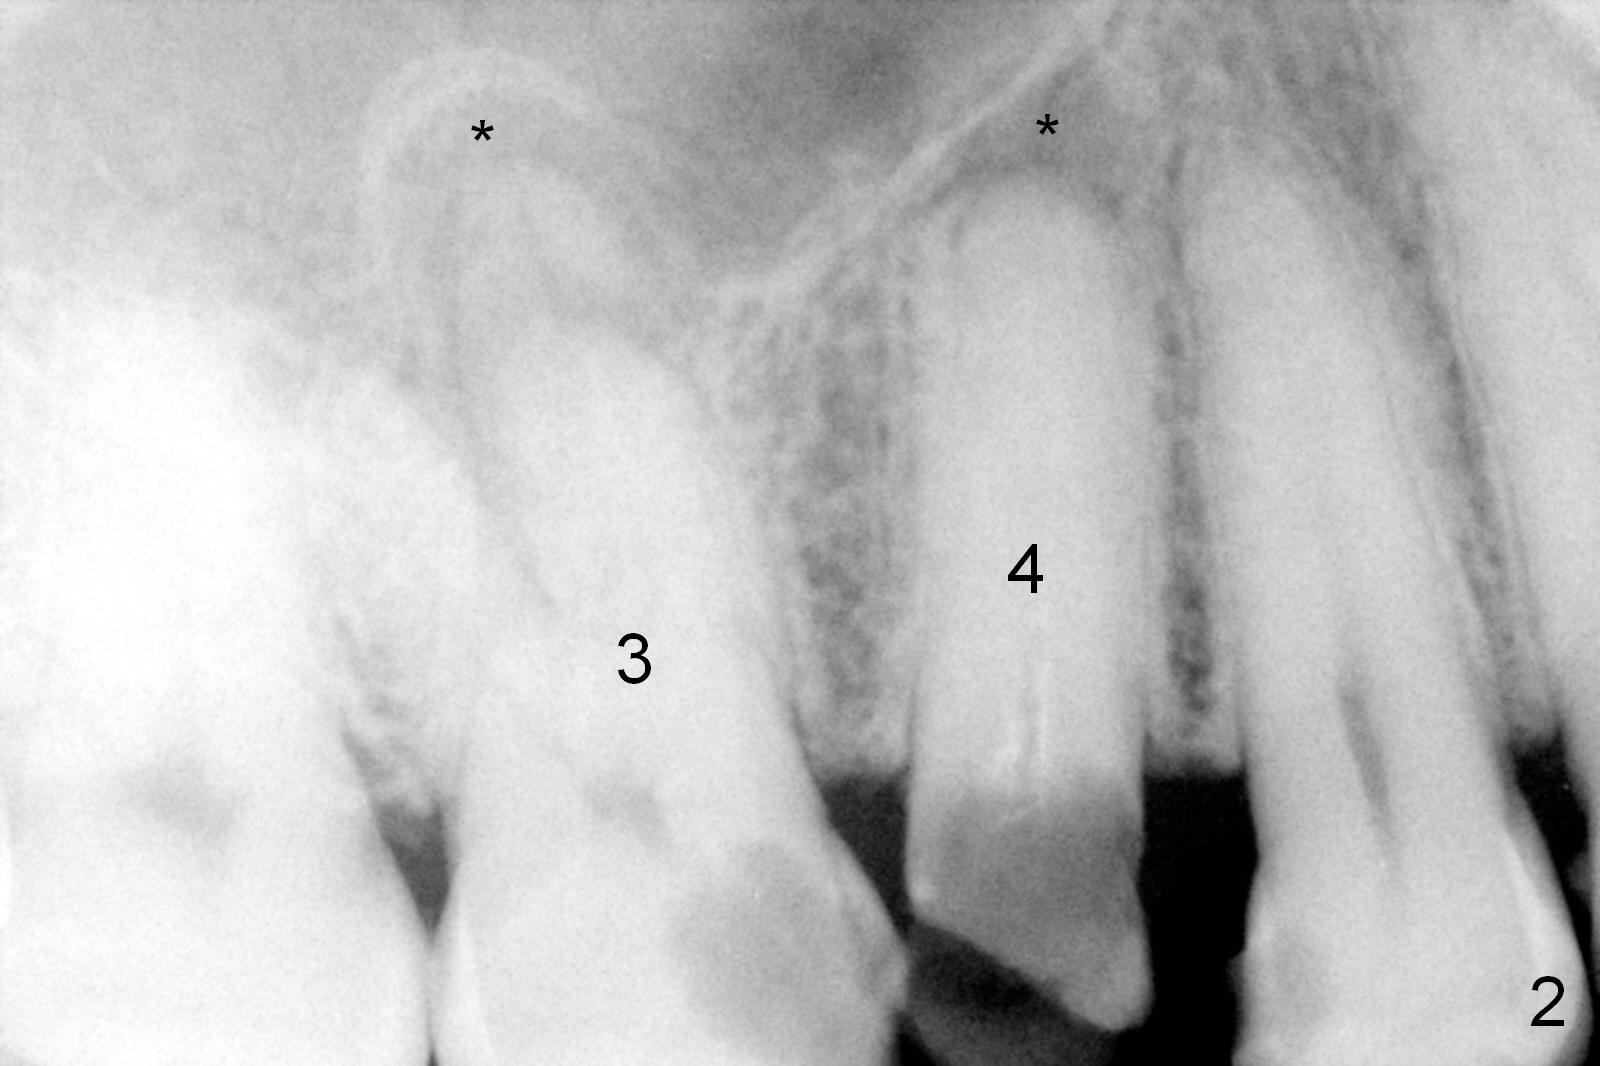

ZC is a 36-year-old man without significant medical history. His chief complaint is "I have Pain sometimes". His oral hygiene is poor (Fig.1). The tooth #3 has large MO caries with periapical radiolucency (*). The tooth #4 is non-salvageable (Fig.1,2). Four months after scaling & root planing, RCT and crown for #3 and extraction of #4 (Fig.3), a 5x8 mm Bicon implant is placed at the site of #4 (Fig.4). Peri-implant space is obliterated 5 months postop (Fig.5). The 2nd surgery is performed to uncover the implant and to place a temporary abutment. Two weeks later, a 5.0x.3.0 mm 0 degree Stealth Abutment 3.0 mm Post is placed (Fig.6). The most recent recall PA shows no bone loss for 5 years 3 months post cementation (Fig.7).